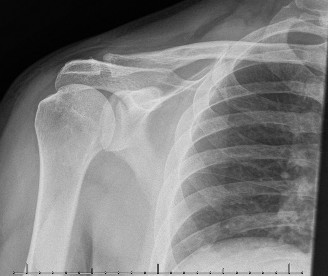

The patient undergoes resection arthroplasty with antibiotic cement spacer and a 6-week course of IV antibiotics. He returns to clinic 4 months later with improved pain, CRP <3, however, on examination he has a positive belly press sign and increased external rotation compared with the contralateral shoulder. Imaging is shown in Figure 2–57.

Figure 2–57

The correct answer is (D). The patient has completed his course of antibiotics and his spacer and is now an appropriate candidate for explanation of the cement spacer with revision shoulder arthroplasty, therefore Choices A and C are incorrect. The patient’s clinical examination findings point to rotator cuff tear (specifically subscapularis) which has occurred in the interval between his obtaining his initial total shoulder arthroplasty and his current examination. Therefore, total shoulder arthroplasty (Choice B) is contraindicated, and the patient should have a reverse total shoulder arthroplasty. Objectives: Did you learn...? Recognize the clinical presentation of a patient with infection after total shoulder arthroplasty?